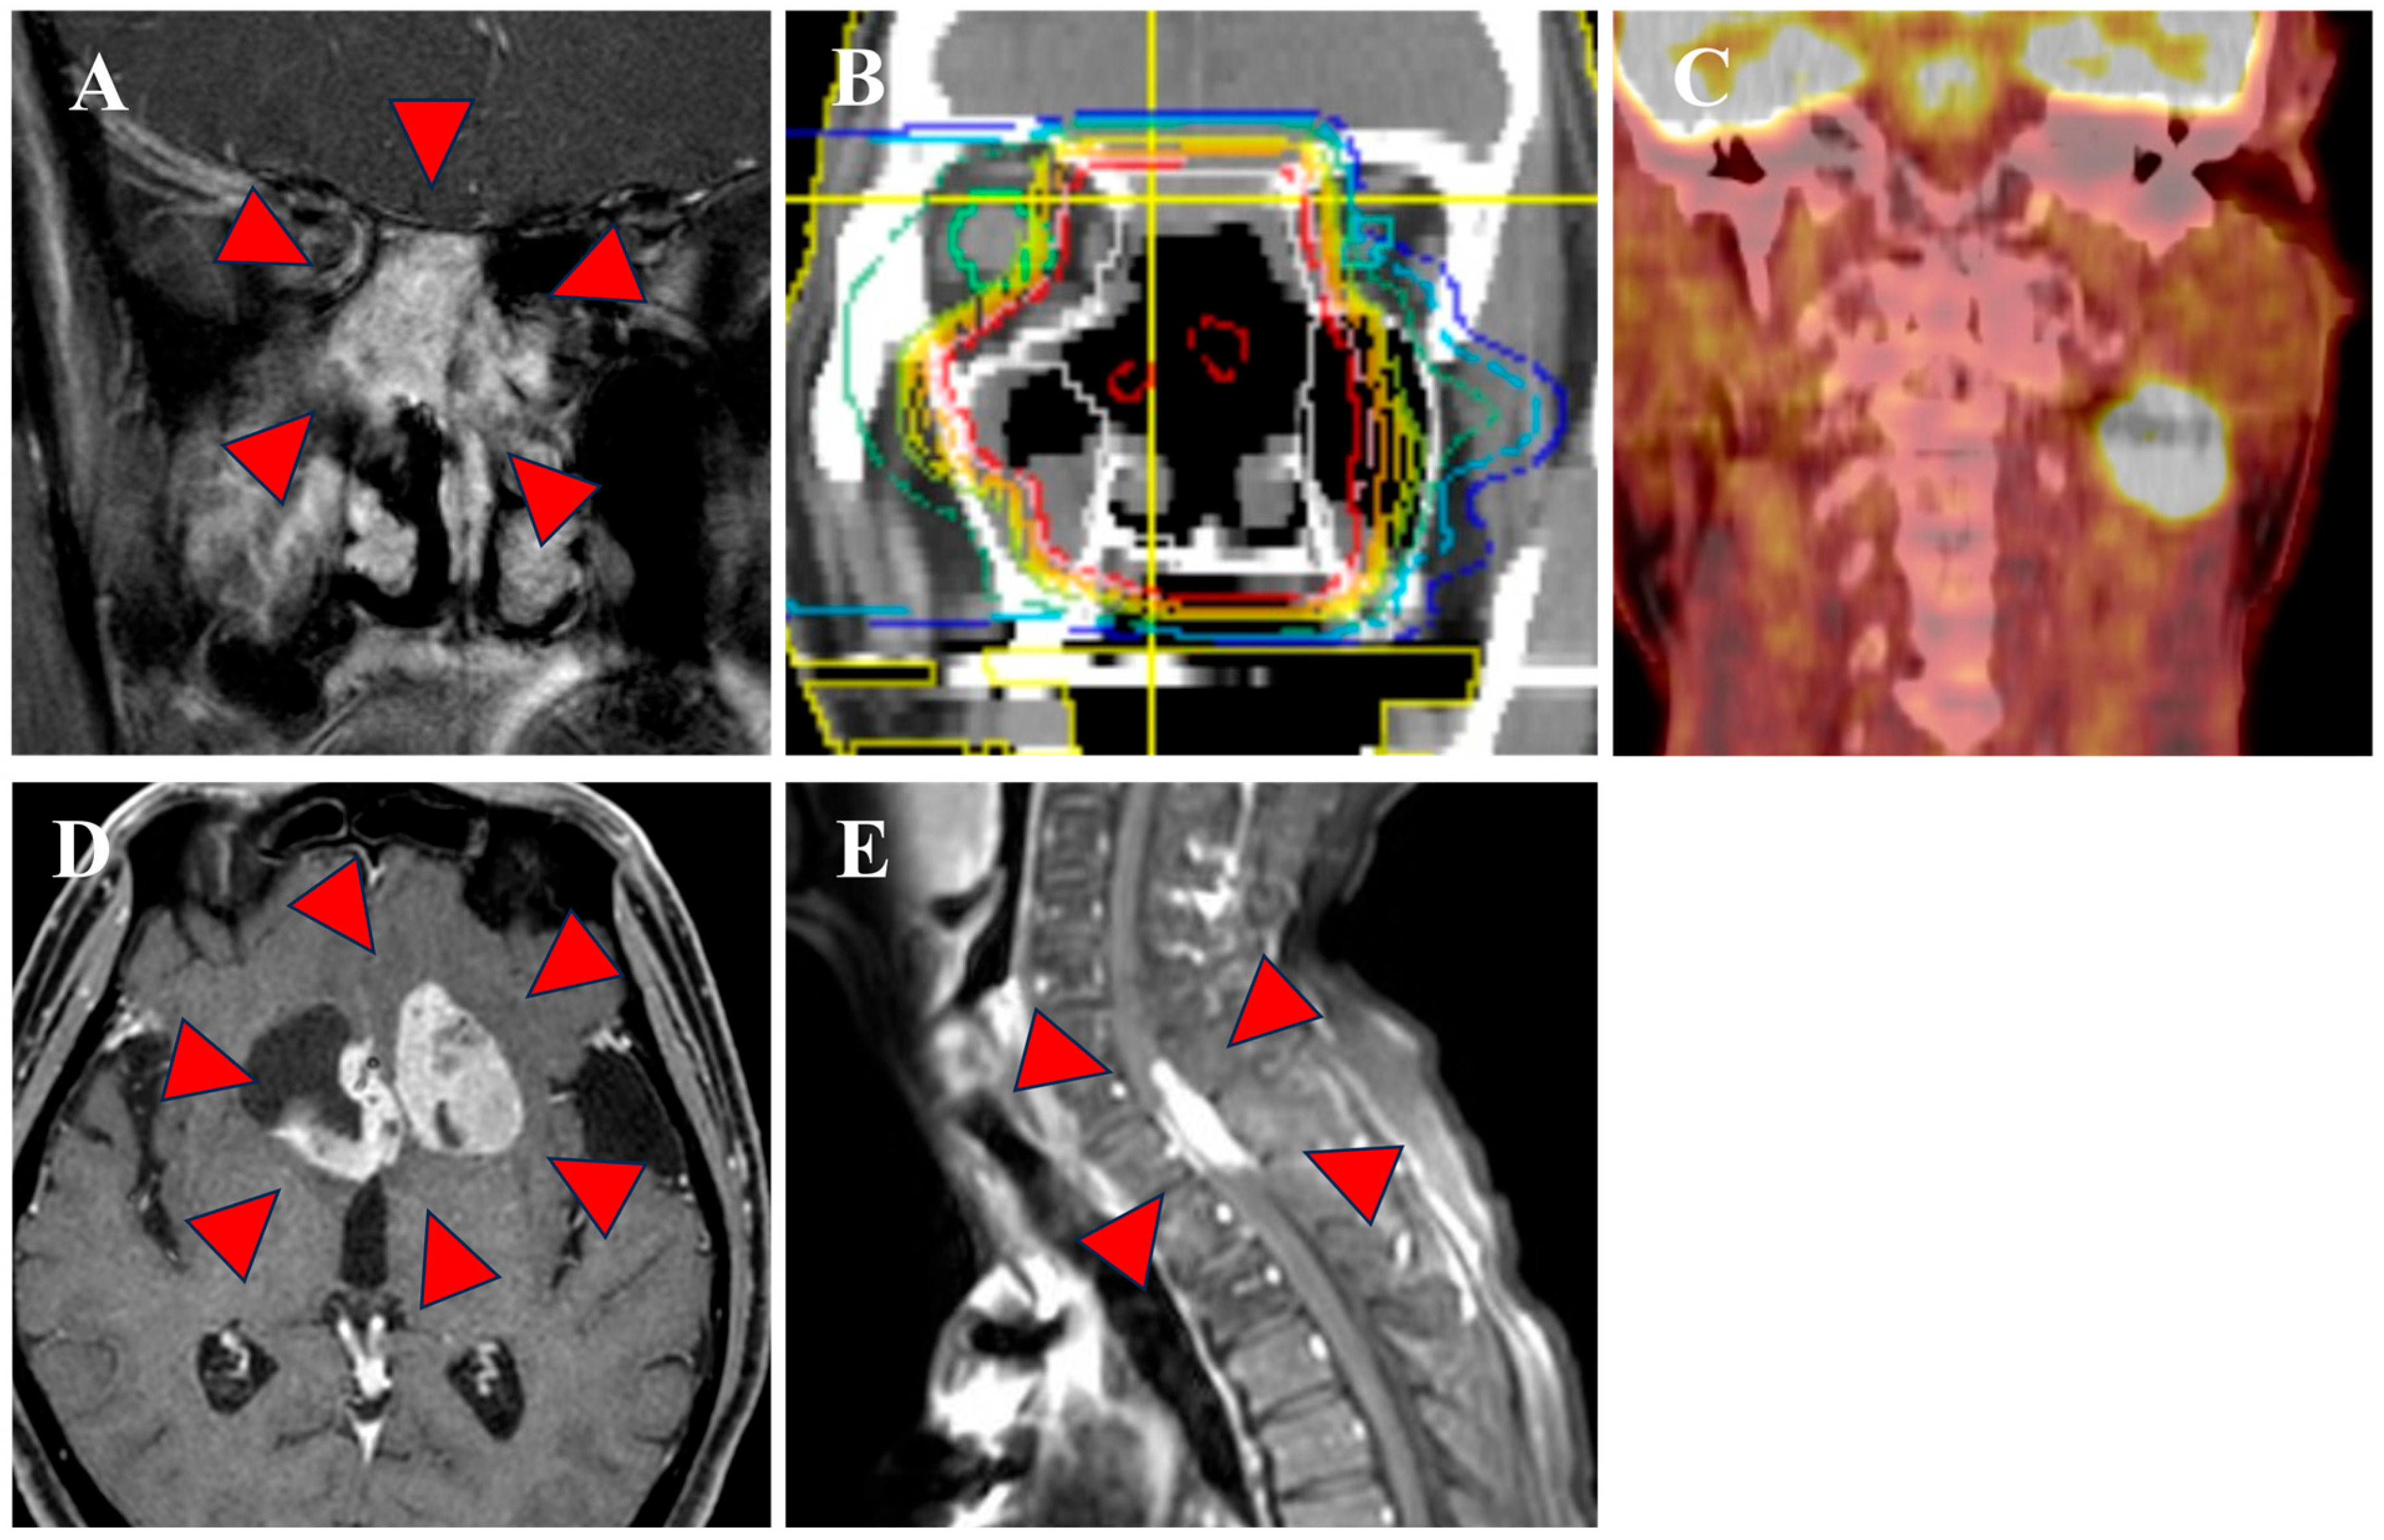

3.1. Clinical Outcomes

3.2. Dosimetric Comparison